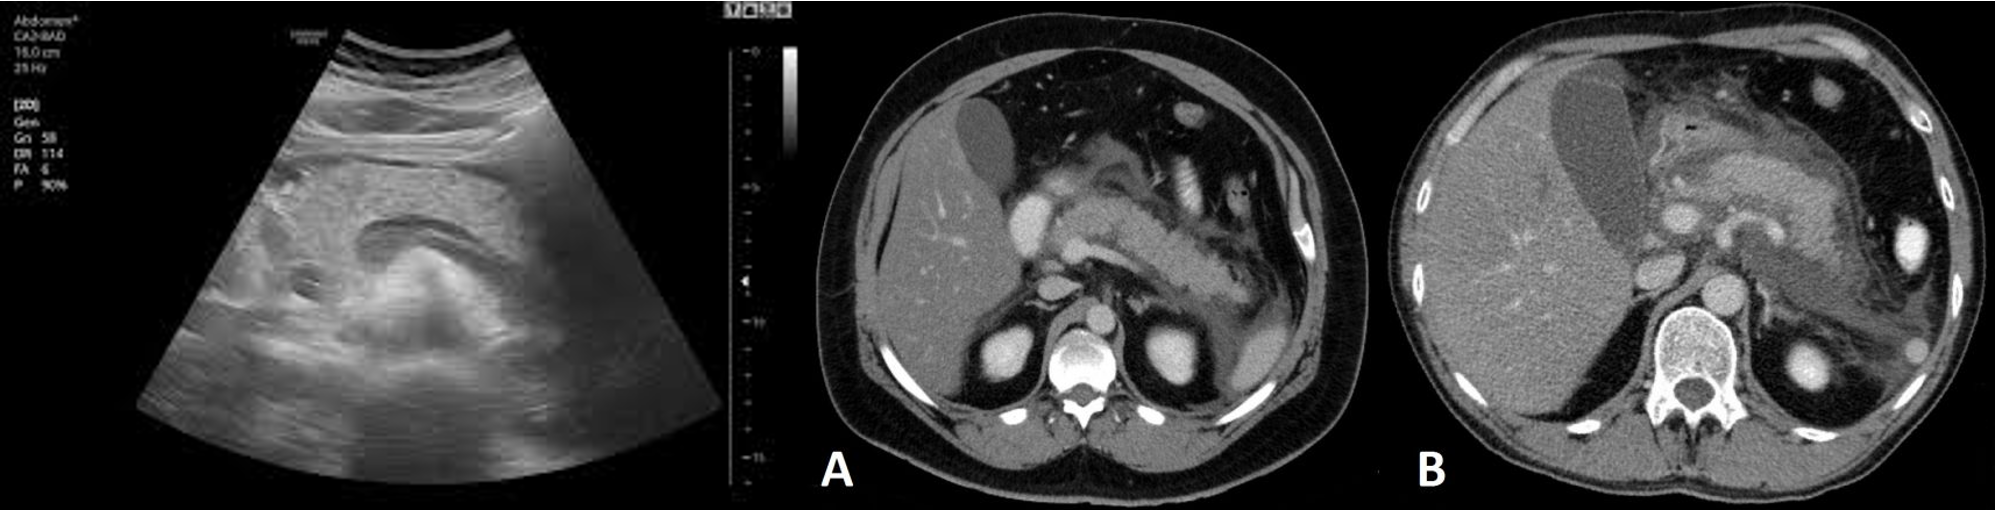

Imaging:

- Chest X-ray: look for pleural effusion, air under the diaphragm in cases of perforated peptic ulcer.

- Ultrasound abdomen: gallstone.

- Abdominal CT: diagnosis, complications of acute pancreatitis, evidence of necrotizing pancreatitis.

CT abdomen Pancreatitis

Although a CT scan may eventually be useful, it will not be as helpful as the other choices at this point. It is best used at 72 hours of illness to assess the degree of pancreatic necrosis in patients with predicted severe disease.